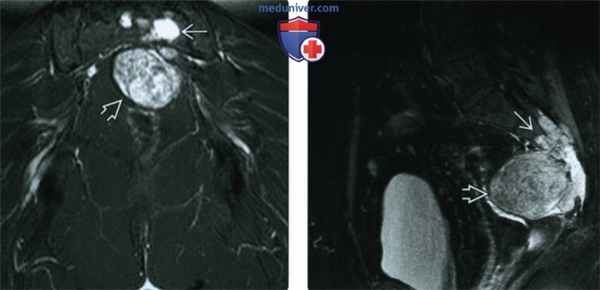

(Слева) МРТ, корональная проекция, режим STIR: у этот же пациента визуализируется неоднородный гиперинтенсивный костный очаг и мягкотканный компонент с похожими характеристиками.

(Справа) МРТ, сагиттальная проекция, режим Т1 с подавлением сигнала от жира, с контрастным усилением: у этого же пациента определяется выраженное контрастное усиление как костного очага, так и мягкотканного компонента. Обратите внимание на то, что ранее была выполнена резекция прямой кишки и матки. При их наличии, они были бы смещены кпереди. Опухоль имеет типичные для хордомы расположение и лучевые признаки.